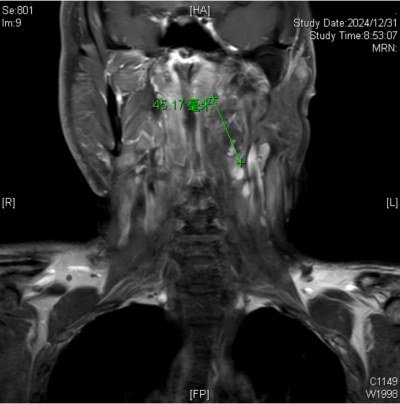

(南华大学附属长沙中心医院)的耳鼻咽喉头颈外科就诊。接诊的杨中纯副主任医师通过颈部增强磁共振成像(MRI)检查,最终确诊导致王永元咽部不适的罪魁祸首竟是咽旁后间隙肿瘤,紧邻口咽部。入院后,经过颈部CTA检查,发现肿瘤将颈内动脉推挤至外侧、变形,经过仔细阅片和详细的术前讨论,耳鼻咽喉头颈外科的医生团队制定了周密的手术计划。

颈部增强磁共振成像(MRI)下发现导致王永元咽部不适的罪魁祸首是咽旁后间隙肿瘤